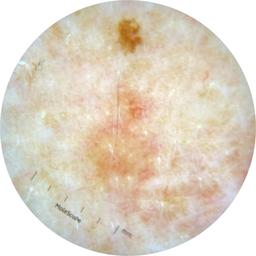

ISIC_5667482

Field Value

acquisition_day 272

age_approx 45

anatom_site_1 Trunk

anatom_site_2 Posterior trunk

anatom_site_general posterior torso

diagnosis_1 Benign

family_hx_mm False

fitzpatrick_skin_type I

image_manipulation instrument only

image_type dermoscopic

lesion_id IL_5659437

patient_id IP_3828705

personal_hx_mm True

sex male